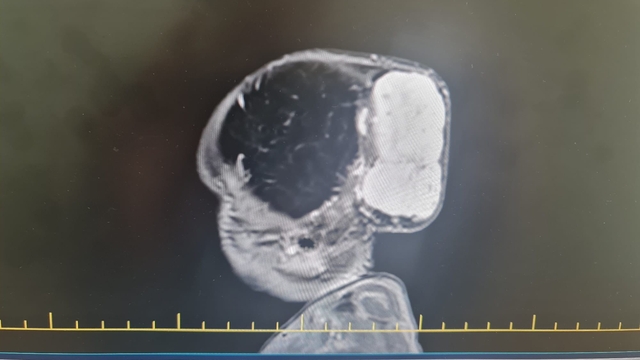

GAZİANTEP’te, beyninde dünyada nadir görülen tümörle dünyaya gelen 1,5 aylık Talha bebek, 4 saatlik ameliyatla sağlığına kavuştu.

Tuğba-Enes Yalçın çiftinin 1,5 aylık çocuğu Talha Yalçın, Gaziantep Şehir Hastanesi'nde başında kitle ile dünyaya geldi. Tetkikler sonucu Talha bebeğin kafatasındaki kitlenin, hızla büyüyen ve beyne baskı yapan 7 x 6,5 x 4 santimetre boyutlarında, dünyada nadir görülen bir tümör olduğu tespit edildi. Talha bebeğin ameliyatını gerçekleştiren Beyin Cerrahi Uzmanı Op. Dr. Ali Yayla, tümörün özelliğinden ve Talha bebeğin yeni doğmuş olmasından dolayı cerrahi stratejilerini yeniden kurarak 4 saatlik ameliyatı tamamladıklarını belirtti.

Tümörün damarlı yapısından kaynaklı kanama riskinin çok olduğu ve ameliyat öncesi girişimsel radyoloji ekibinin hastaya bir embolizasyon işlemi yaptığı ve tümörün kanlanmasını azalttığı söylendi. Operasyonun 4 saat sürdüğünü belirten Dr. Yayla, “Hastamız başında dev bir kitle ile doğdu. Yaptığımız tetkikler ve görüntülemeler sırasında tümörün hızla büyüdüğünü ve kafatası kemiklerini harap ettiğini, beyne de baskı yaptığını gördük. Ameliyat planladık fakat bu tümörün özelliğinden dolayı çok fazla damar yapısı vardı, kanaması çok fazlaydı ve tümörün kanama riski nedeniyle hayati risk bu cerrahi işlemde yüksek düzeydeydi. Bu nedenle cerrahi stratejimizi yeniden kurduk. Buna göre basamaklandırılmış ve multidisipliner bir yaklaşım sunduk. Öncesinde girişimsel radyoloji ekibi hastaya bir embolizasyon işlemi yaptı ve tümörün kanlanmasını azalttı. Hemen 1 gün sonra plastik cerrahi ve beyin cerrahisinden oluşan bir ekiple yaklaşık 4 saat süren ameliyatla tümörün tamamını başarılı bir şekilde çıkardık. Hastamız bundan herhangi bir zarar görmedi ve sağlığı da gayet iyi seyrediyor. Ailemize sağ salim teslim ettik çocuğumuzu" ifadelerini kullandı.

Dr. Yayla, ameliyata dair detayları anlatarak, "Bu işlemin arka planında çalışan yeni doğan çocuk, yoğun bakım çocuk, hematoloji, beyin cerrahisi, plastik cerrahi ve anestezi olmak üzere büyük bir ekip var. Doktorundan hemşiresine sağlık çalışanlarından hastane yönetimine kadar herkes 1,5 ay süre boyunca gayret gösterdi ve sonunda çocuğumuz sağlıklı bir şekilde ailesine teslim edildi. Tümörün boyutu 7x6,5x4 santimetre çaplarındaydı. Bu büyüklükte bir tümör dünyada bu yaş grubunda nadir görülmüştür. Bu operasyonu başarılı bir şekilde Gaziantep Şehir Hastanesi’nde yapmış olmak da bizim için büyük bir gurur oldu. Bizim açımızdan taburcu olması için herhangi bir sorun yok. Bugün 4'üncü günü ama biraz daha gözetim altında kalıp güvende olmasını istiyoruz. Dördüncü günü tamamladık, beşinci gün taburcu olabilir hastamız” dedi.